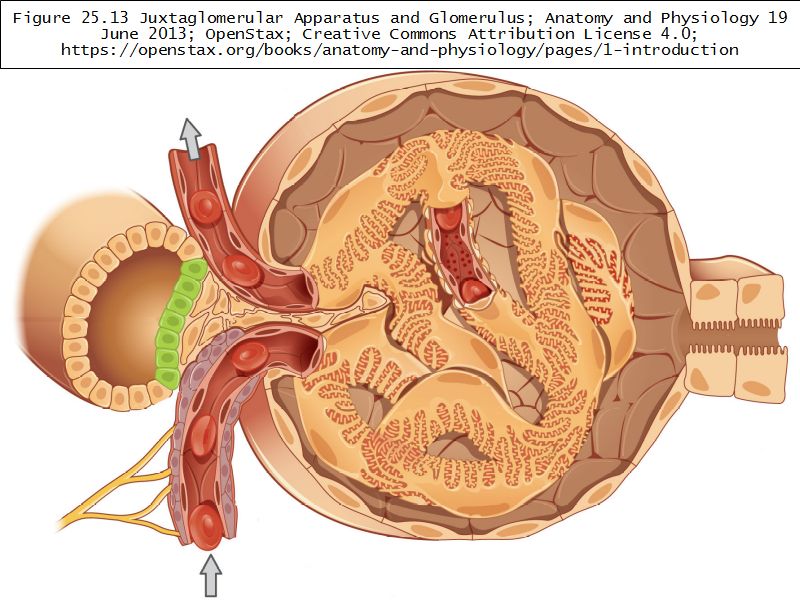

Juxtaglomerular complex

Area where distal convoluted tubule return to glomerulus and pass through the notch between the afferent and efferent arterioles. Modification of the wall of the tubule and afferent arteriole and presence of specialised cells in the connective tissue.Modifications

- Distal convoluted tubule

- Macula densa

- Narrow epithelial cells

- Nuclei densely packed

- CT cells

- Laci cells

- Similar to mesangial cells

- Afferent arteriole

- Modified smooth muscle cells

- Juxtaglomerular cells

- Secretory function

Capillaries

- Supported by

- Mesangial cells

- Mesangial matrix

- Phagocytic

- Maintain basement membrane

- Remove macromolecular deposits

Mesangial cells

- Around capillary loops at vascular pole

- Phagocytic

- Maintain basement membrane

- Remove macromolecular deposits